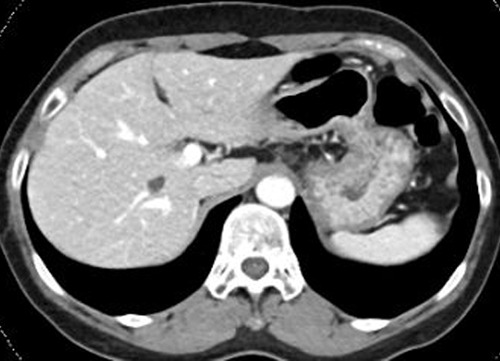

복부 CT는 X-ray(엑스레이)보다 훨씬 정밀한 영상을 찍을 수 있어서, 다양한 장기의 상태를 한눈에 볼 수 있어!

🔹 간 질환 – 지방간, 간경화, 간암 등 확인 가능

🔹 췌장염·췌장암 – 췌장에 염증이 생기거나 종양이 있는지 체크 가능

🔹 담낭염(담석증) – 담석(돌)이 생겼는지, 담낭에 염증이 있는지 확인

🎗 간암, 췌장암, 대장암, 신장암 등 초기 단계에서 발견 가능!

🎗 양성종양 or 악성종양(암) 판별 – 혹이 생겼다면 악성인지 양성인지 확인할 수 있음